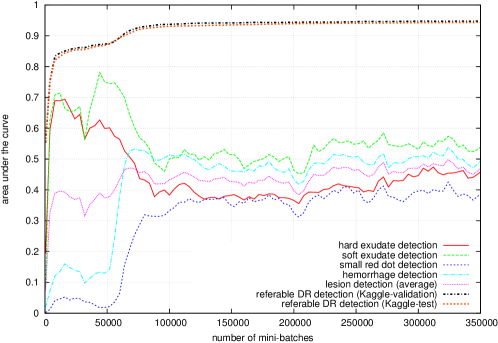

Figure 5 reports the performance of ‘net B’ at different checkpoints stored during the training process. The hue-constrained sensitivity criterion is used, with or without sparsity maximization. Performance at the image level was assessed using a ROC analysis in the validation subset of Kaggle-train (‘Kaggle-validation’ for short), as well as in Kaggle-test: the area under the ROC curve is used as performance metric. Performance at the lesion level was assessed using a free-response ROC (FROC) analysis in the DiaretDB1 dataset. FROC curves are usually not bounded along the x-axis (the number false positives per image): we used as performance metric the area under the FROC curve for , divided by (with = 10). Performance is computed for each lesion type independently, and an average performance metric is also computed. The influence of , the factor of the cost function, on the performance at the image level ( in the Kaggle validation set) and at the lesion level ( in the DiaretDB1 dataset), is given in table 2.

5.6 Ensemble Learning

As commonly done in machine learning competitions (Russakovsky et al., 2015), an ensemble of ConvNets was used to boost performance. As less commonly done, all ConvNets in the ensemble originate from the same network, but with parameter values obtained at different checkpoints during the learning process. This way, training the ensemble is not significantly more computationally intensive than training a single ConvNet. As shown in Fig. 5, individual lesion types are not optimally detected after the same number of iterations. So, the idea was to export parameter values from the ConvNet when:

-

hard exudates were optimally detected (network — iteration 4,000 for ‘net B’),

2.

-

small red dots were optimally detected (network — iteration 208,000 for ‘net B’),

4.

-

lesions were optimally detected on average (network — iteration 328,000 for ‘net B’),

6.

Besides analyzing the pixel-level performance of the final ConvNets, we also analyzed the pixel-level performance while the ConvNets are being trained (see Fig. 5 for the ‘net B’ ConvNet). It turned out to be quite instructive. By analyzing performance at the image level alone (the area under the ROC curve in the Kaggle validation set), all we can see is that 1) performance quickly reaches a satisfactorily level (), then 2) slowly increases for many iterations, 3) experiences a second leap to reach a very high level () and finally 4) reaches its optimal state () very slowly. By analyzing the heatmaps, we understand that the ConvNet very quickly learns to detect exudates and cotton-wool spots (or ‘soft exudates’). The second performance leap is observed when the ConvNet learns to detect hemorrhages. The final fine-tuning stage correlates with the progressive discovery of microaneurysms (or ‘small red dots’) by the ConvNet. Interestingly, lesions were discovered in the same order regardless of the ConvNet structure (‘net A’, ‘net B’ or AlexNet). The order in which lesions are discovered by ConvNets makes sense: the most obvious lesions (the largest and the most contrasted) are detected first and then the ConvNet discovers that more subtle lesions (which are more difficult to capture) are in fact more useful to make a diagnosis. By the way, for ‘net A’ and ‘net B’, we observe that the detection performance of bright lesions (exudates and cotton-wool spots) decreases when red lesions (hemorrhages and microaneurysms) are discovered: red lesions are indeed usually enough for detecting referable DR. This behavior is not observed for AlexNet: the reason probably is that red lesions are not detected well enough (see Table 3), due to the low resolution of input images (224 224 pixels). The main difference between the two plots of Fig. 5 (with or without sparsity maximization) is observed in the latest stages of training. As the artifacts are removed by enhancing the sparsity of the heatmaps, the detection performance at the pixel level increases for every lesion type. We hypothesized that maximizing the sparsity of the heatmaps would also speed up the training process, by reducing the search space. However, we did not observe such a behavior.